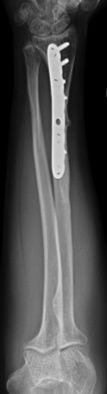

Las fracturas desplazadas o inestables precisarán de reducción cerrada o abierta en quirófano, asociado en algunos casos a osteosíntesis (Figura 10). Las fracturas localizadas en la unión metafiso-diafisaria distal son inestables y en muchos caos requieren tratamiento quirúrgico (Figura 11).

Figura 10: a, b-Fractura de radio y cúbito distal inestable en paciente de 12 años. c- Reducción y estabilización mediante agujas de Kirschner. c-Control final al año de la cirugía.